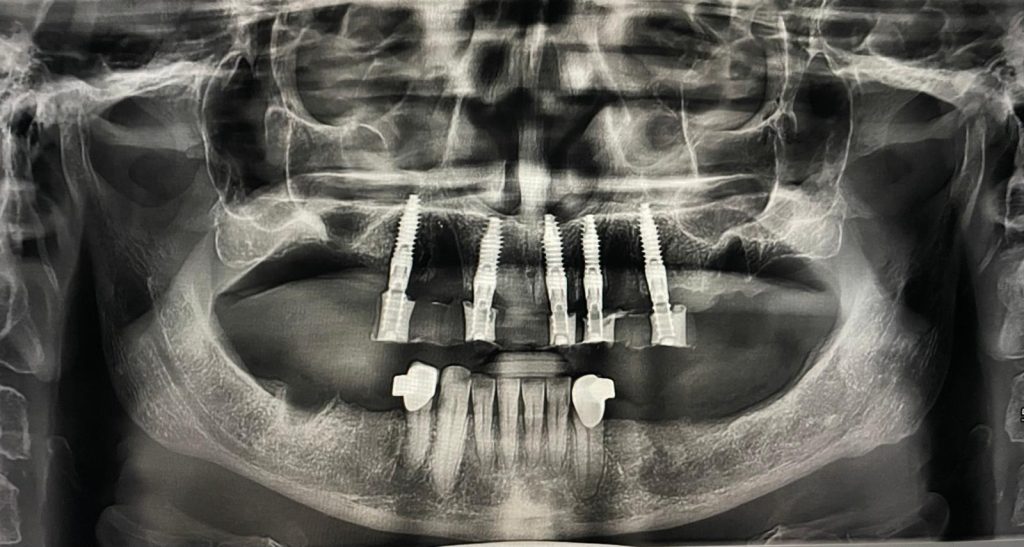

Questa settimana vi presento un caso di riabilitazione immediata dell’arcata superiore eseguita in chirurgia computer guidata con l’utilizzo di dime scomponibili.

L’intervento ha previsto l’estrazione degli elementi dentari, l’inserimento di 5 impianti nell’arcata superiore, il montaggio delle torrette provvisorie e la ribasatura del provvisorio nel cavo orale.